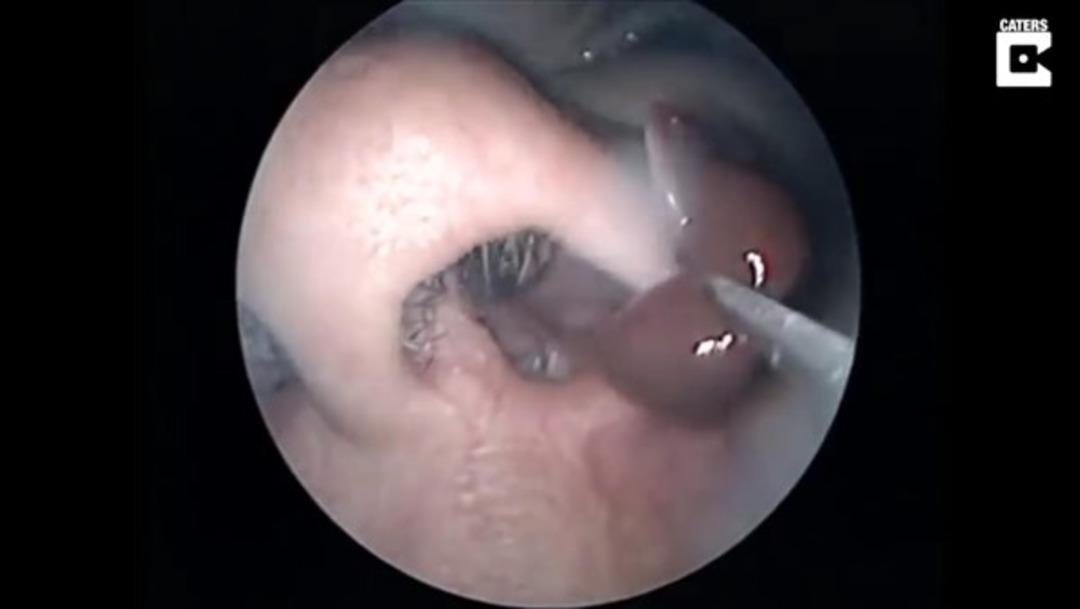

Burnunda garip bir hareketlilik hisseden hasta doktora göründü.

Doktor ise ufak bir operasyon yaptı.

Yüzerken burnuna kaçan şey doktorları bile şaşırttı